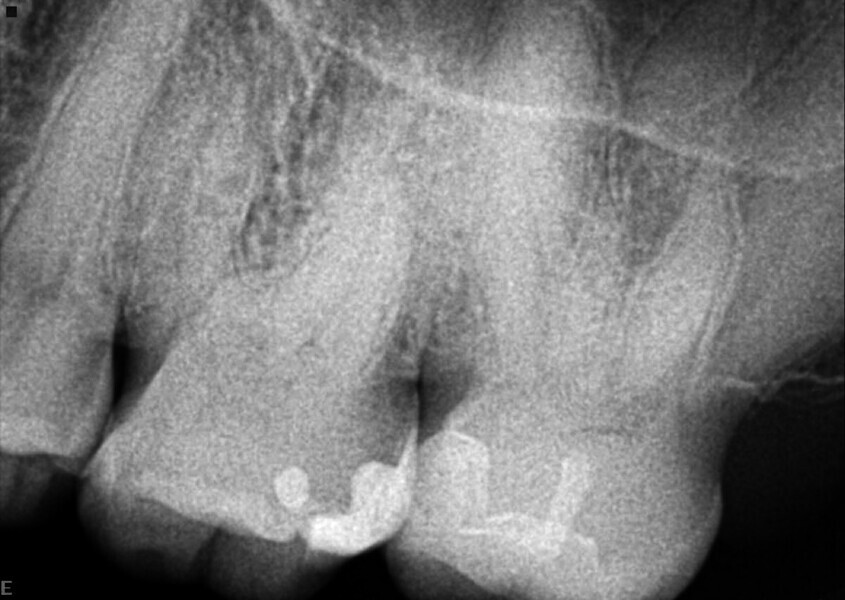

Le même patient présentait également une fistule vestibulaire au niveau de la furcation de la molaire inférieure antagoniste, dont la cause était une position trop élevée des contacts occlusaux, due à un manque d’ajustement après la pose de l’inlay sur la molaire supérieure, (Fig. 8).

Ce défaut de traitement avait provoqué l’activation de la substance P et entraîné la calcification pulpaire de la molaire supérieure, ainsi que l’inflammation irréversible de la molaire inférieure — des effets de microtraumatisme.

Le mode endodontique de DTX Studio Clinic (Fig. 9) a été utilisé pour examiner chaque image et coupe transversale, et déterminer l’origine de la fistule au niveau de la molaire inférieure. Une possibilité était peut-être le complexe des canaux latéraux observé dans la partie coronaire de la racine distale (Fig. 10). Les limes Traverse et ZenFlex ont été utilisées selon la même séquence que celle du cas 1 pour procéder au traitement canalaire, puis une obturation tridimensionnelle a été effectuée à l’aide du système éléments IC (Fig. 11).